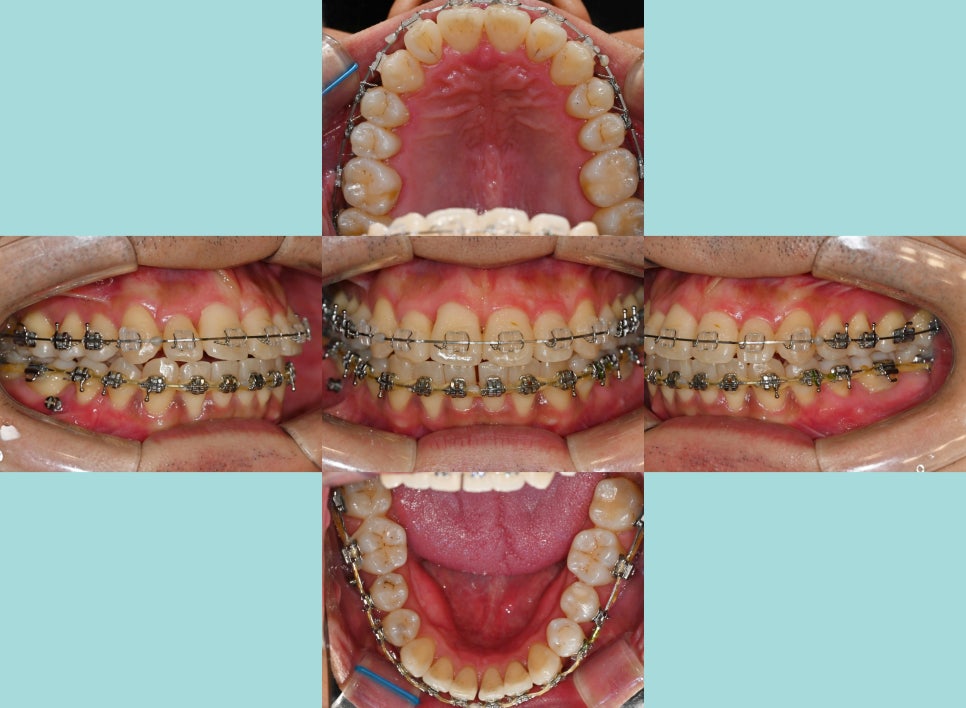

실제로 이렇게 앞니 뻐드렁니와 총생 등

갖가지 문제를 가지고 있는 분들께서는

평소 구강 관리가 어렵습니다.

제대로 칫솔질이 되지 않으니

치석도 자주 쌓여 잇몸에 염증 발병률도 높아집니다.

좀 더 자세히 내부를 들여다봤을 때,

되게 어지럽게 배열되어있는 모습을 볼 수 있습니다.

특히나 전치부에 집중된 총생(crowding)은

배열을 들쑥날쑥하게 만듭니다.

사진에서 보여지듯이 12번은

반대교합의 형태도 나타내고 있었는데요.

다른 곳들은 윗니가 아랫니를 덮는 반면에

오른쪽 아랫니 송곳니 부분이 위쪽의 12번을

덮고 있는 형태로 반대교합을 보여줍니다.